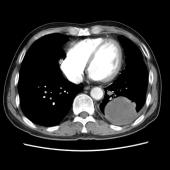

[影像描述]

左肺下叶可见高密度肿块影,边界清晰,边缘不规则,左肺下叶支气管局部截断,增强后病灶边缘轻度强化,中心未见明显强化;左侧胸腔内可见液性密度影;纵隔内未见明确肿大淋巴结影。